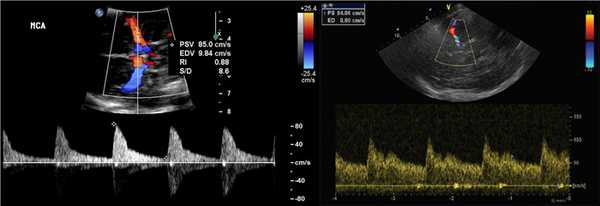

СМА красная, спектр выше базовой линии, так как поток направлен к датчику, TAMX 122 см / с. Передняя мозговая артерия сегмента A1 синяя, спектр ниже базовой линии, поскольку поток от датчика направлен к средней линии мозга.

![]()

Наиболее часто используют среднюю по времени максимальную скорость (TAMX), также называемое средней скоростью. Пиковая систолическая скорость (VS) и конечная диастолическая скорость (VD) также могут быть измерены.